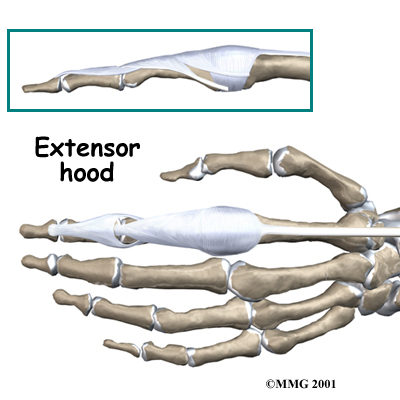

The tendons that allow each finger joint to straighten are called the extensor tendons. The extensor tendons of the fingers begin as muscles that arise from the backside of the forearm bones. These muscles travel towards the hand, where they eventually connect to the extensor tendons before crossing over the back of the wrist joint. As they travel into the fingers, the extensor tendons become the . The extensor hood flattens out to cover the top of the finger and sends out branches on each side that connect to the bones in the middle and end of the finger.